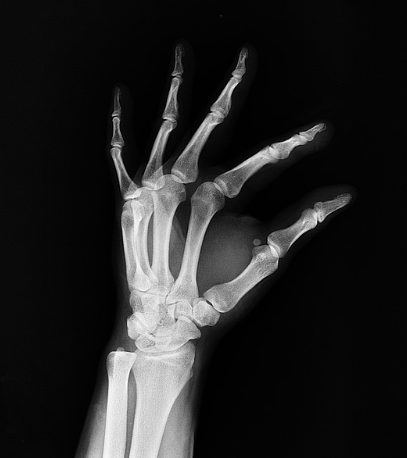

✅ 2) X-ray (엑스레이) 촬영 📷

✔ 골막 비대 & 뼈 성장 이상 확인 가능

📢 Tip: 진단을 위해 X-ray 촬영 후 추가적인 정밀 검사가 필요할 수도 있음!